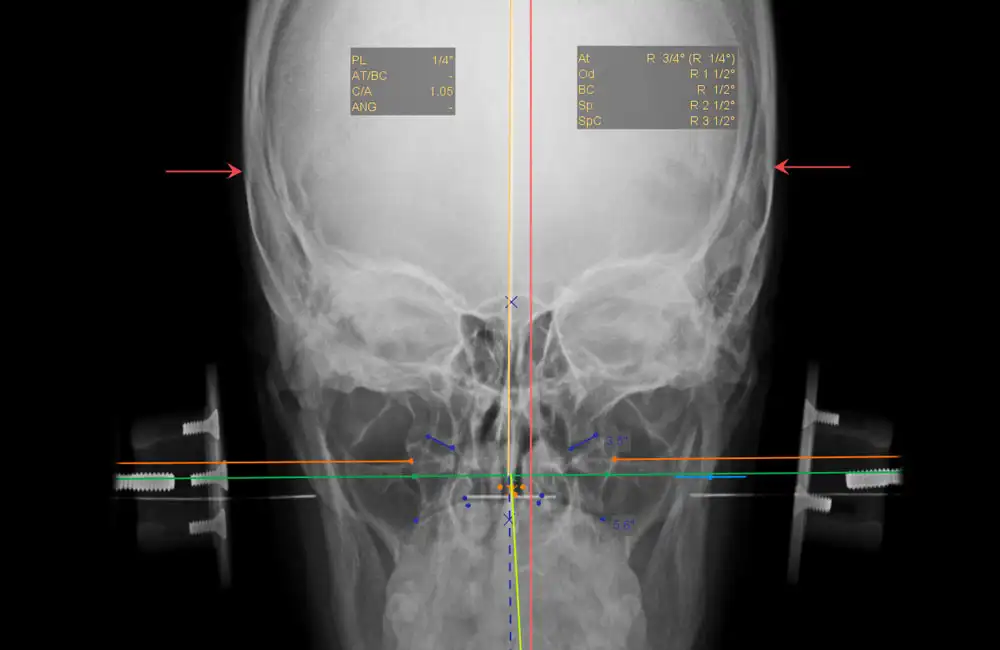

The dicomPACS® Upper Cervical (NUCCA) Chiropractic Tool Set was developed in close collaboration with leading NUCCA experts from the United States and Canada. It provides everything required for fast and highly precise diagnostics in the upper cervical spine. Specialized NUCCA templates such as the cephalometer, grid, circumscale, and relatoscope support a familiar workflow while ensuring maximum accuracy.

Using manual point marking, the software automatically generates midlines, reference points, curves, and angles, significantly improving the efficiency of diagnosis and treatment planning. The NUCCA Tool Set is complemented by all essential standard chiropractic tools, including distance and angle measurements, Cobb angles, and marker points—delivering a comprehensive, professional NUCCA analysis within a single, integrated solution.

Automatic generation of midlines, reference points, curves, and angles based on manual point marking.

NUCCA-specific lines and structures such as the atlas plane line and S-line for accurate diagnostics.

All essential measurement and marking functions, including angle, distance, and Cobb measurements.